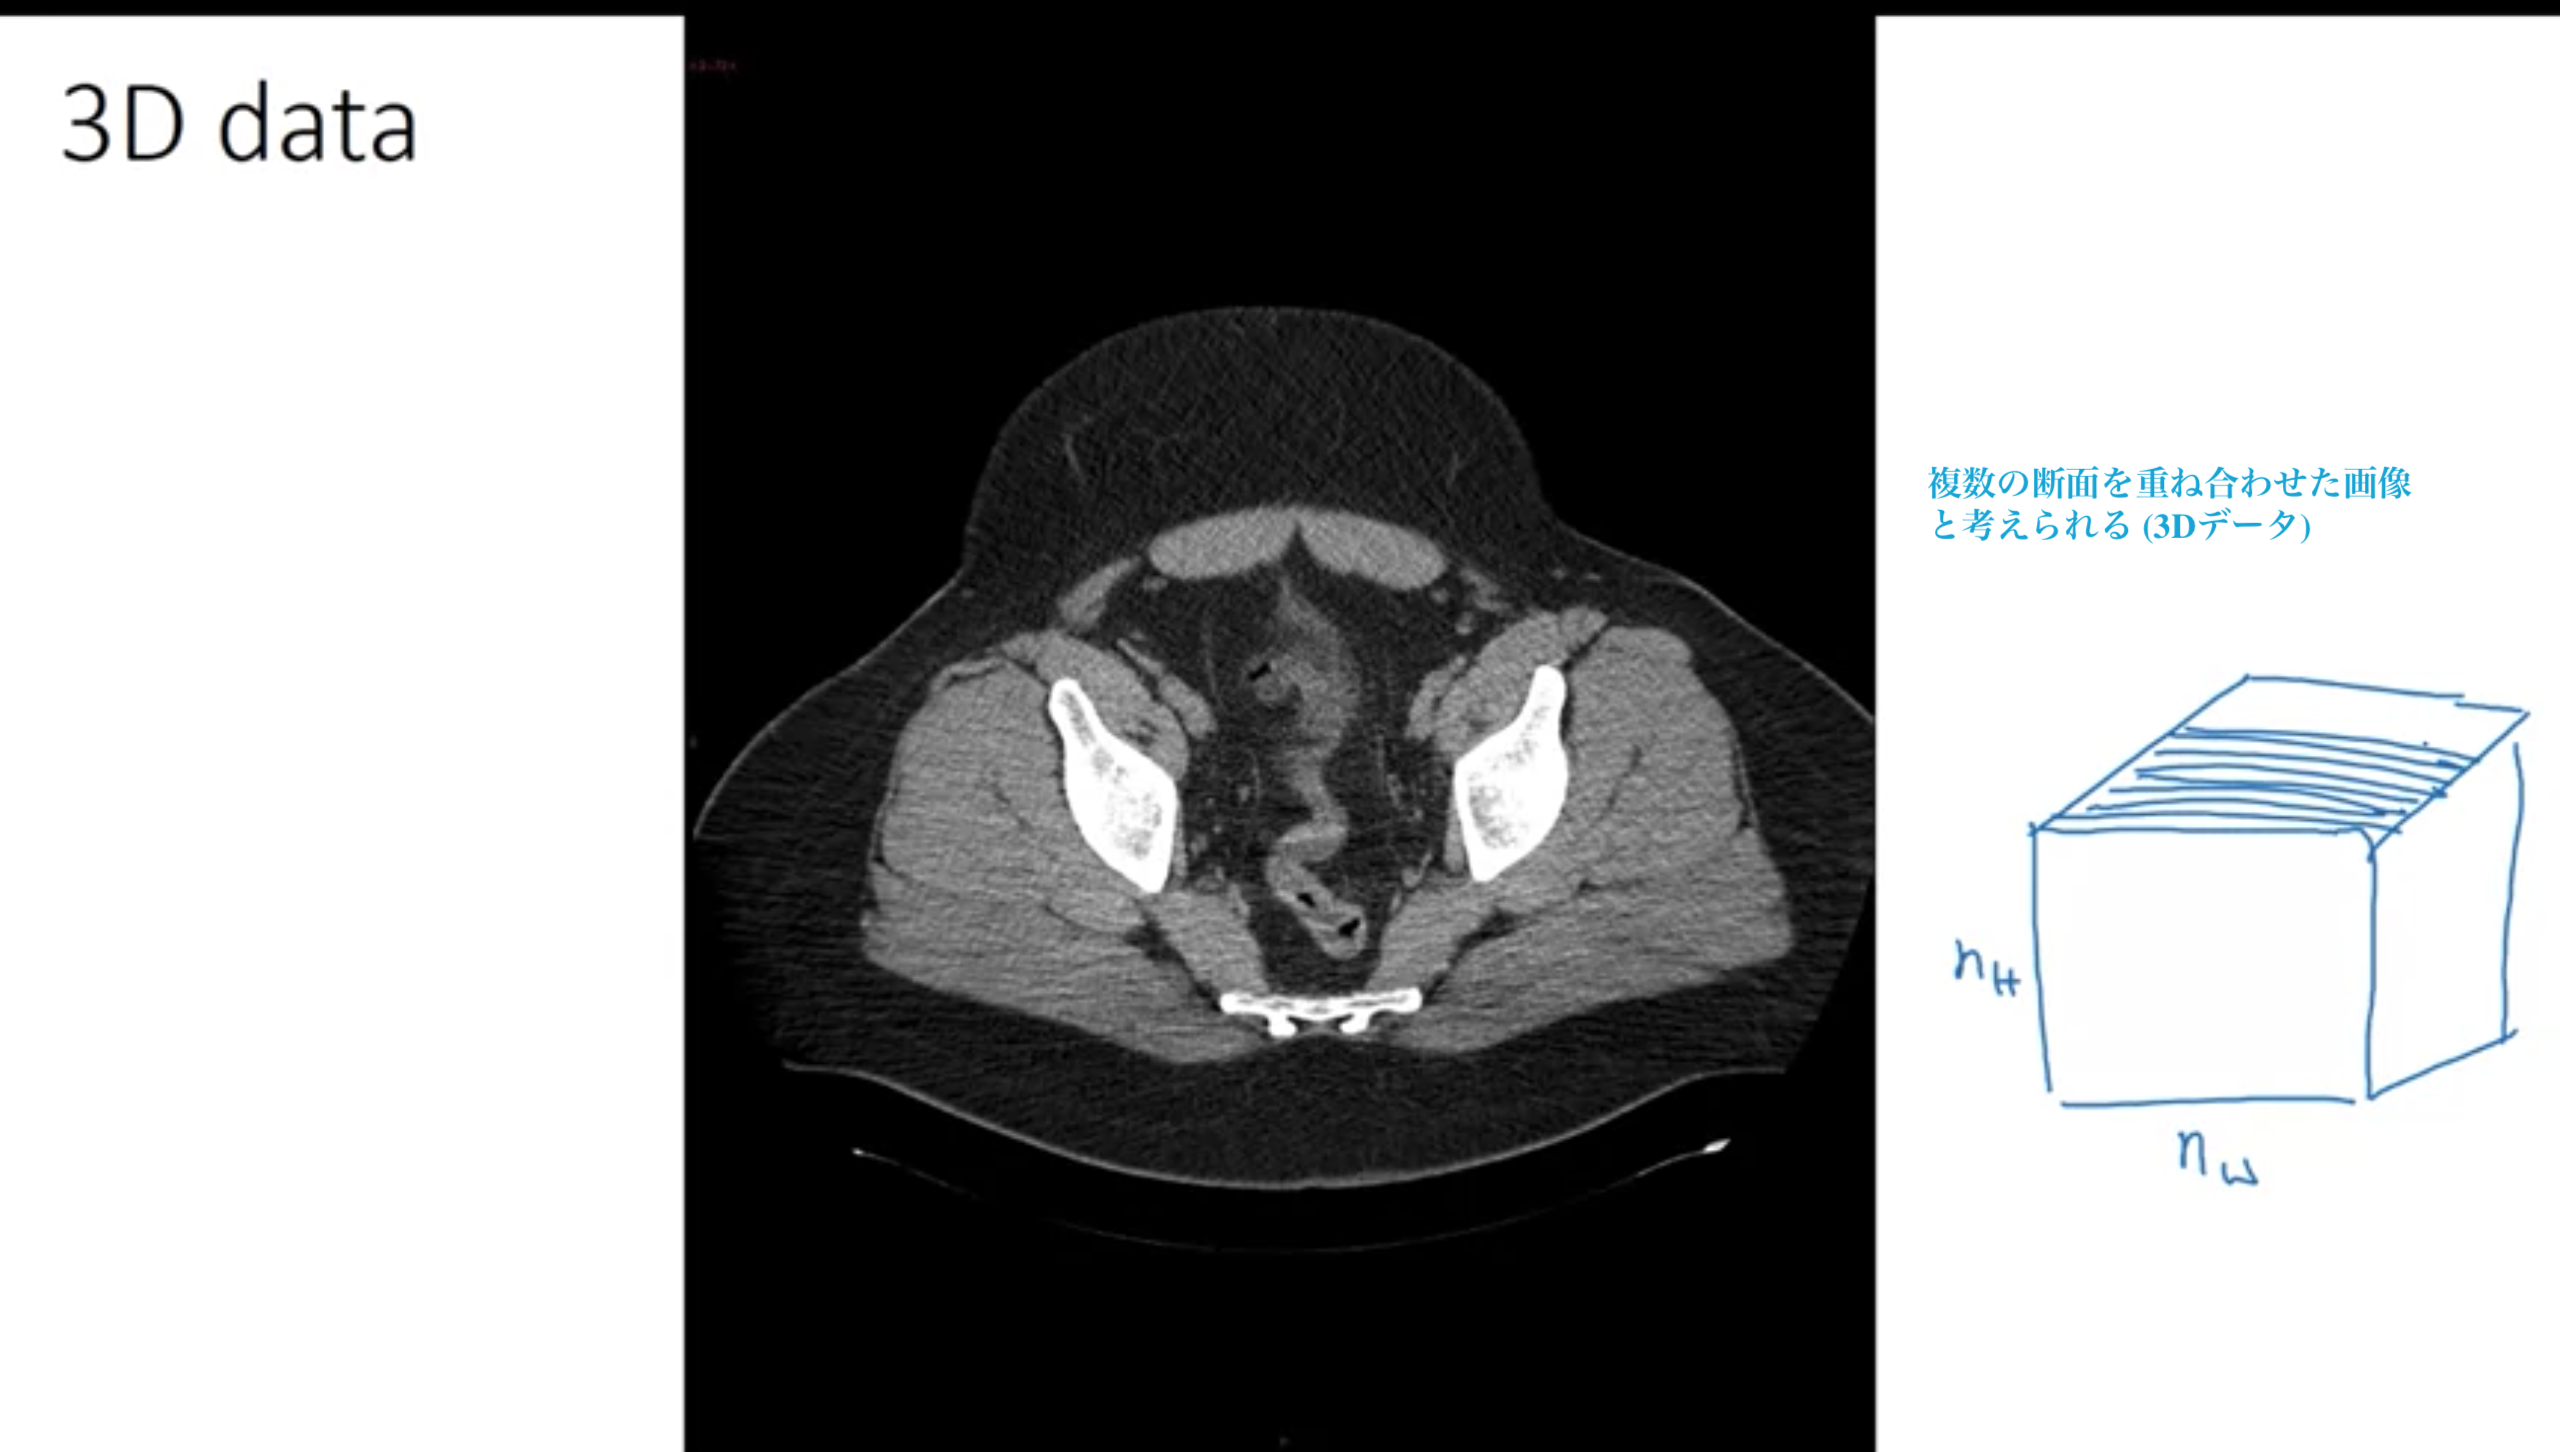

・X線によるCTスキャン (体の奥行きの断面)

・映画データ (映画の時間が異なる断面 映画内の人の動きを検出)

体全体に渡って、断面図を何重も重ね合わせた構造をとる、つまりデータは根本的に3次元 (高さ×幅×深さ×カラーチャンネル数)

X線によるCTスキャン